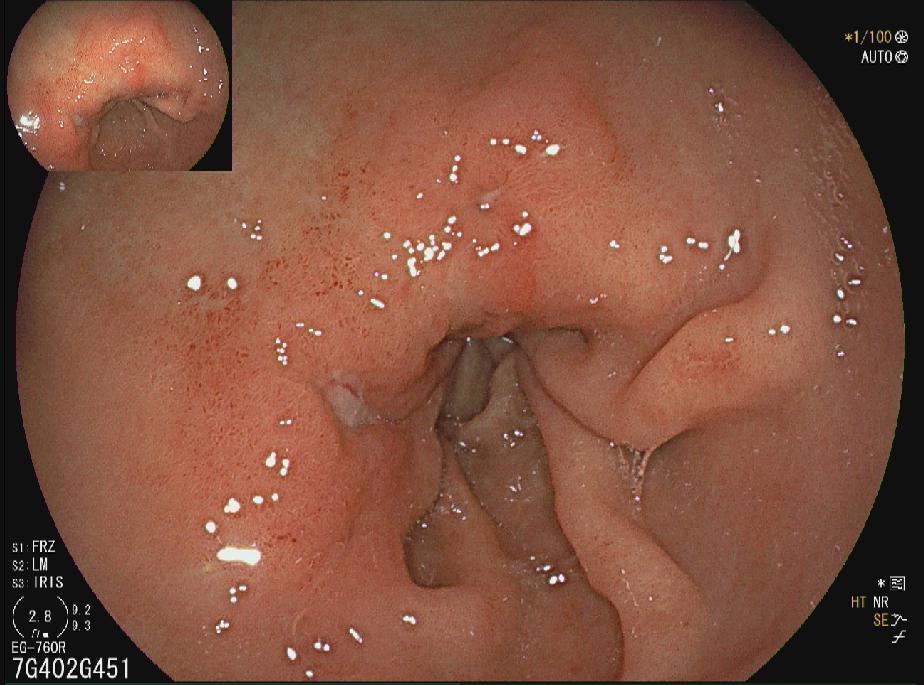

十二指肠球部溃疡

胃窦多发溃疡

胃窦溃疡

胃角溃疡

HPA感染鸡皮样胃炎

胃癌